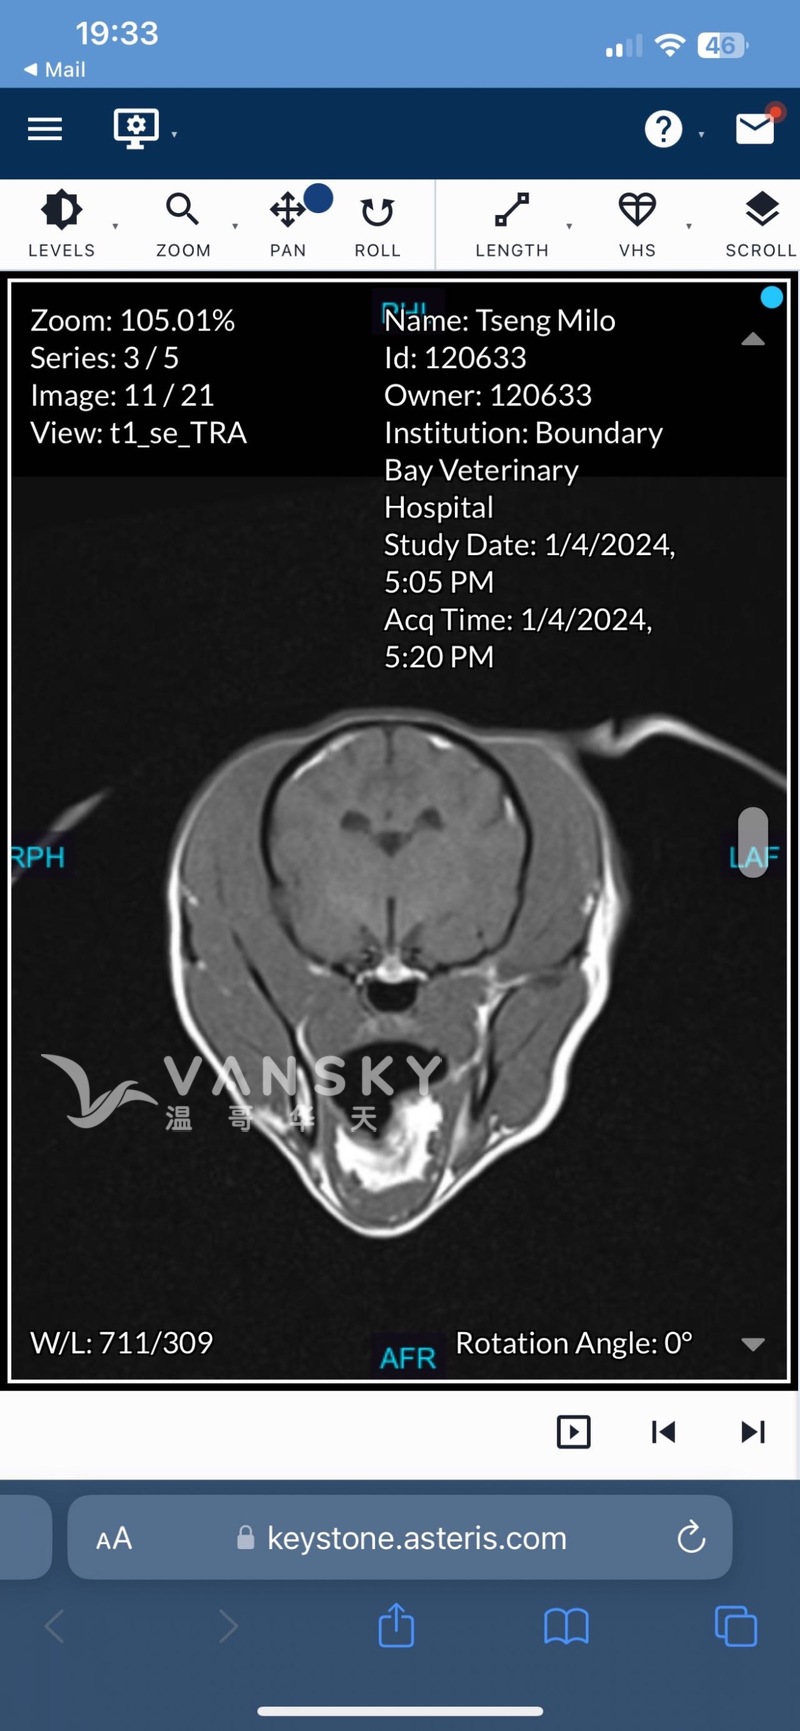

泰迪狗狗只有三岁大,我跟我女朋友一直都细心照顾,不知道为何突然感染了急性隐球菌脑膜炎。我们两周前发现它走路只能左转,马上就医,医生马上做了各项检查,说隐球菌已经感染到了脑部,说现在得住院先观察和保守治疗和用药,因为这个病十万分之一才会得,我们很想救她,可是我们都刚刚出社会工作,能力实在有限,开销有点太大了,加起来已经花了10000刀,但我们又不忍心放弃。希望各位好心人如果有能力的话给予一点点的支持,就算给一点点语言的鼓励也好,谢谢了